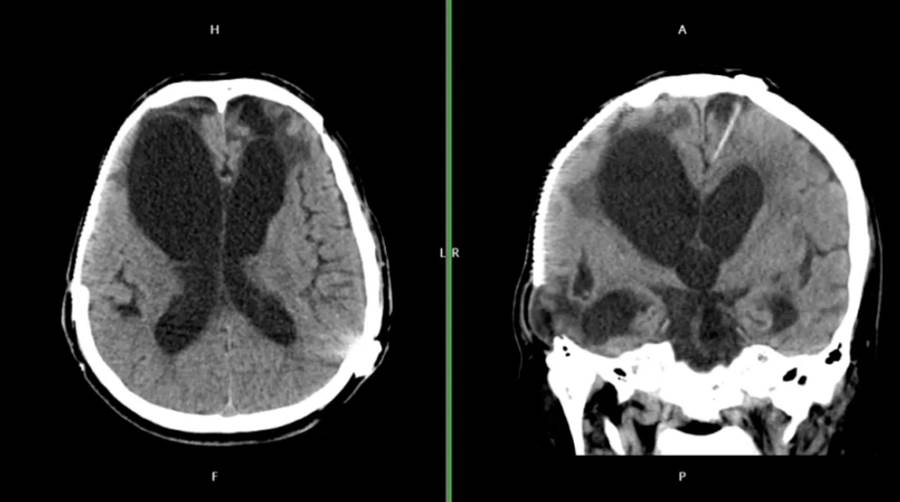

新光醫院急診醫學科醫師解釋,腦傷後常見「清醒期」:

「特別是硬腦膜下出血,患者可能先意識清醒數小時,等血腫擴大才突然惡化。這就是為什麼交通事故後即使當下沒事,也必須觀察72小時。」